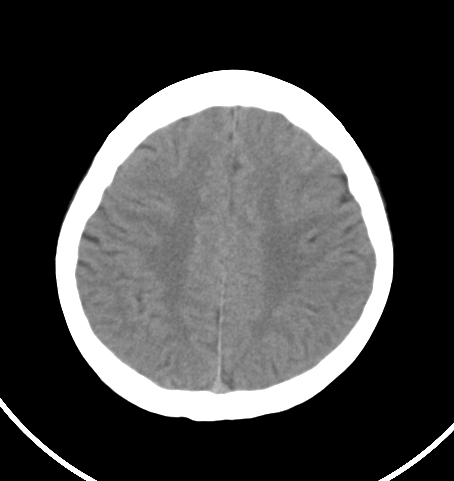

病人女 35岁 自述头晕 头痛

双侧基底节区及右侧丘脑区多发点状钙化,周围未见水肿及占位征象.余未见明显异常.考虑:脑囊虫病<囊虫的退变或死亡期>请结合有无相关病史.

以下是引用苯小孩在2007-4-20 15:47:00的发言:[br]双侧基底节区及右侧丘脑区多发点状钙化,周围未见水肿及占位征象.余未见明显异常.考虑:脑囊虫病<囊虫的退变或死亡期>请结合有无相关病史.

颅内有散在钙化

脑囊虫病理性钙化。